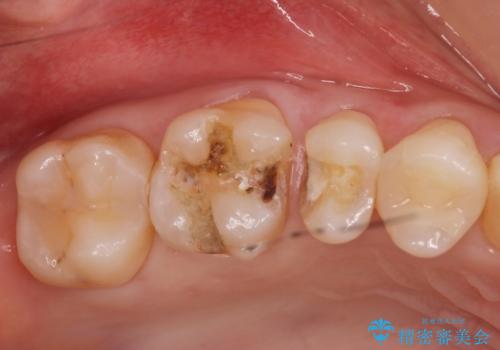

銀の詰め物がある2歯を白くしたい。

- 銀の詰め物を白くしたいとの事で来院。

拡大鏡下で詰め物を外しう蝕がないことを確認して、e-maxインレーにて治療しました。